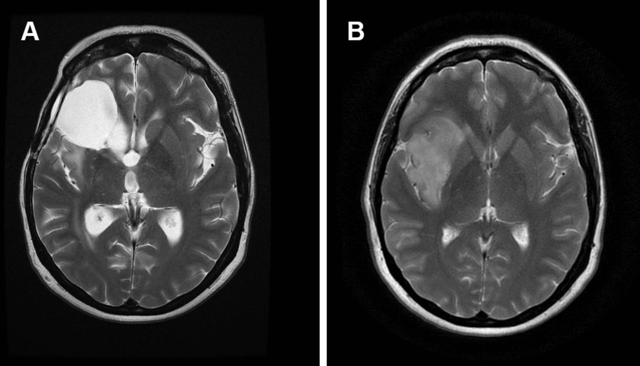

根据脑胶质瘤的生长潜力和侵略性,它们被指定为不同等级。脑胶质瘤的病理级别是根据肿瘤的组织结构和细胞特点由病理科医生于术中或术后在显微镜下做出的,一般分为3~4个级别,依次为胶质瘤1、2、3、4级。其中1级代表相对不严重的瘤种,4级代表比较严重的肿瘤。脑胶质瘤通常简称为“低级”或“高级”。

大多数高级或更具侵略性的脑胶质瘤已经发展出自己的血液供应,并倾向于浸润。 肿瘤还可以打破肿瘤附近区域的血脑屏障。 此外,这些肿瘤通常在手术切除后重新生长,通常被称为复发性脑癌。

INC国际神经外科医生集团提示,对于不同级别的胶质瘤,治疗策略上也会有所不同:1级胶质瘤因没有浸润,应尽力争取全切,因为全切可以治愈,否则还会复发。2级胶质瘤治疗较为复杂,因为不是全部2级肿瘤一经诊断就立即手术,二级胶质瘤往往是肿瘤细胞和正常神经细胞混合生长且生长缓慢,如果肿瘤位于重要功能区域在切除肿瘤同时会将正常神经细胞一同切除导致病人术后功能障碍,笔者不建议对这样病人马上实施外科治疗,我有一些功能区低级别胶质瘤患者诊断后经随访3~5年后再手术也获得一样的治疗效果,但重要的是为他们赢得了3~5年的近于正常的生活和工作时间,但对于非功能区、有占位效应的和成熟的二级胶质瘤可尽早手术。3级胶质瘤在保留功能的基础上尽量切除肿瘤,是要将显示增强的区域切除,因为这些区域是肿瘤较恶的部分残留会很快复发。4级胶质瘤因肿瘤生长迅速和向周围浸润严重在保留功能前提下应尽量完全和扩大范围切除包括一些非功能区的水肿带。